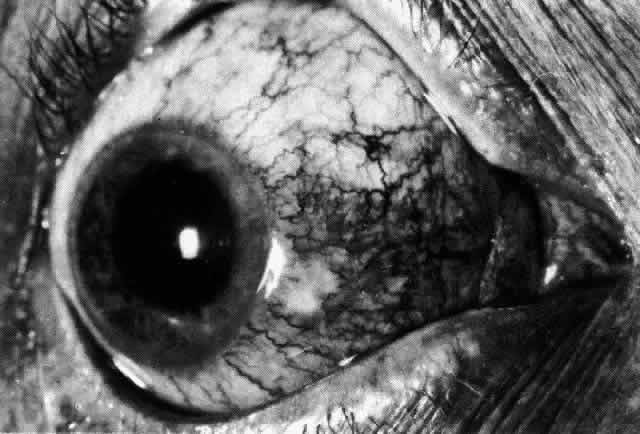

Simple and nodular episcleritis differ in their clinical courses, but in both the edema and infiltration are entirely within the episcleral tissues. The sclera is not involved. The maximum congestion is in the superficial episcleral network, with some slight congestion of the conjunctival vessels and deep episcleral vessels (Fig. 10). The intraocular structures are not involved in either variety, nor is the visual acuity affected. Anterior segment fluorescein angiography reveals a normal vascular pattern but a very rapid flow rate, with the whole transit of the dye being completed within 2 or 3 seconds (Figs. 11 and 12).

Fig. 10. Maximum congestion in the superficial vascular plexus in episcleritis. The conjunctival and deep episcleral networks are separated from the deep plexus by edema and infiltration in the episcleral tissue. (Watson PG, Hayreh S, Awdry P: Episcleritis and scleritis. Br J Ophthalmol 52(3):278–279, 1968)

The redness of simple episcleritis may be intense, varying from a fiery-red or a brick-red discoloration to a mild red flush, but it does not have the bluish tinge that is seen in scleritis. The distribution is usually sectorial but can involve the whole anterior segment of the globe. The episcleral vessels are engorged but retain their normal radial position and architecture (Figs. 13 and 14; Color Plate 1A). In simple episcleritis, there is a diffuse edema of the episcleral tissues. These tissues are sometimes infiltrated with gray deposits that appear yellow in red-free light. Surprisingly, the eye is rarely tender to the touch.

Fig. 13. Infiltration of the episclera in which the superficial episcleral vessels show maximal congestion. Conjunctival vessels are slightly congested, as is the deep episcleral plexus, whose irregular criss-cross pattern can be seen deep to the radially arranged superficial episcleral plexus.